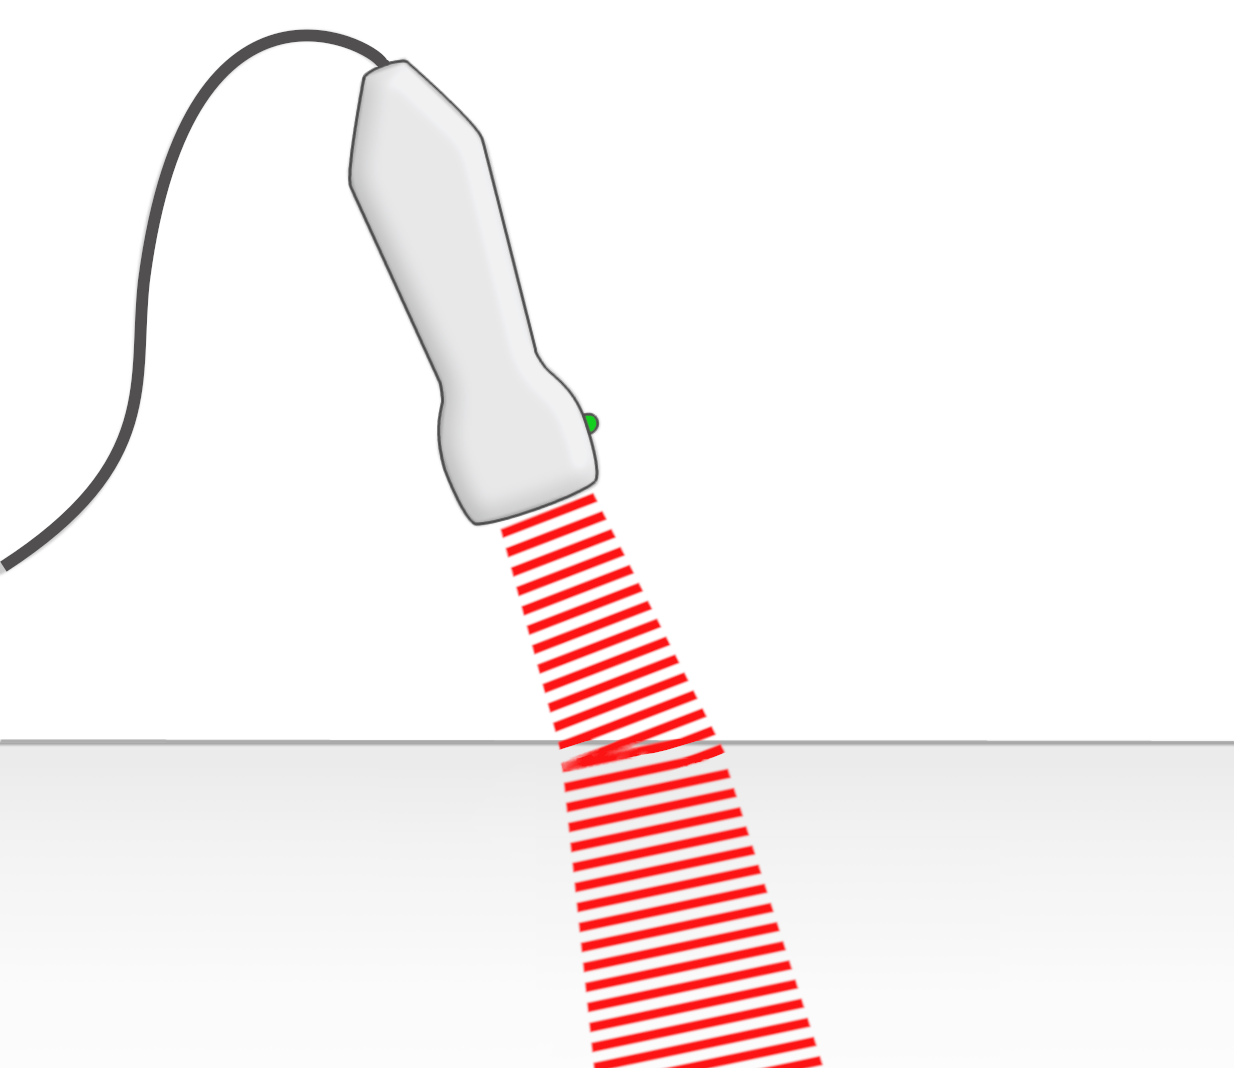

Medizinischer Ultraschall: Schallköpfe

Linearschallkopf, Konvexschallkopf, Sektorschallkopf

Edler-Echokardiographie